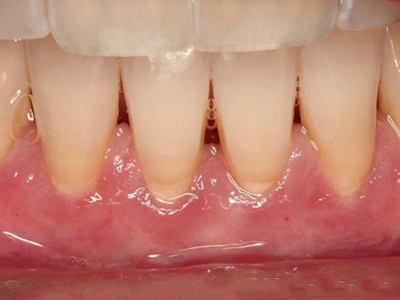

牙龈退缩露出淡黄色牙根图

牙龈退缩患者的牙龈退缩后,淡黄色牙龈明显露出。若进一步发展,易使对应位点的牙槽骨发生骨吸收,可能诱发龋齿、牙龈敏感、菌斑堆积等。